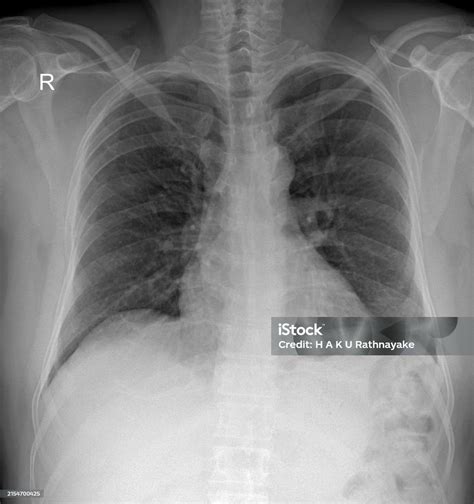

Alright, so how do we actually find these pesky thoracic spurs ? Enter the X-ray, your trusty medical sidekick. An X-ray is a type of imaging test that uses a small amount of radiation to create pictures of the inside of your body, in this case, your thoracic spine. It’s a quick and painless procedure that can reveal a lot about the condition of your bones and joints. When it comes to thoracic spine bone spurs , X-rays are usually the first step in diagnosing the problem. The images can clearly show the presence of these bony growths, their size, and their location relative to your vertebrae and other structures in your spine. It’s like a snapshot of your spine, allowing doctors to identify any abnormalities.

Now, let’s talk about what you can expect during an X-ray. The process is pretty straightforward: you’ll typically be asked to stand or sit in front of the X-ray machine while a technician positions you to capture the necessary views of your spine. You might be asked to hold still and take a deep breath during the scan to ensure the images are clear. The whole process usually takes just a few minutes, and you won’t feel anything during the X-ray itself. The technician will take multiple views, such as frontal (from the front), lateral (from the side), and sometimes oblique (at an angle), to get a complete picture of your spine. These different angles help the doctor to get a good look at all the different parts. After the X-ray, a radiologist will review the images and create a report, which your doctor will then use to help you figure out what to do next.

So, when you see those X-ray images, what are you looking for? Well, thoracic spine spurs will appear as small, bony protrusions along the edges of your vertebrae. They might look like tiny spikes or irregular bumps. The radiologist will also be looking at the overall alignment of your spine, the spaces between your vertebrae, and any signs of other conditions like osteoarthritis or degenerative disc disease. They’ll assess the size, shape, and location of the spurs to determine their potential impact on your health. However, an X-ray can only show the bone structure and not the soft tissues like muscles, ligaments, and nerves. If your doctor suspects nerve compression or other soft tissue issues, they might recommend additional imaging tests, such as an MRI or CT scan.